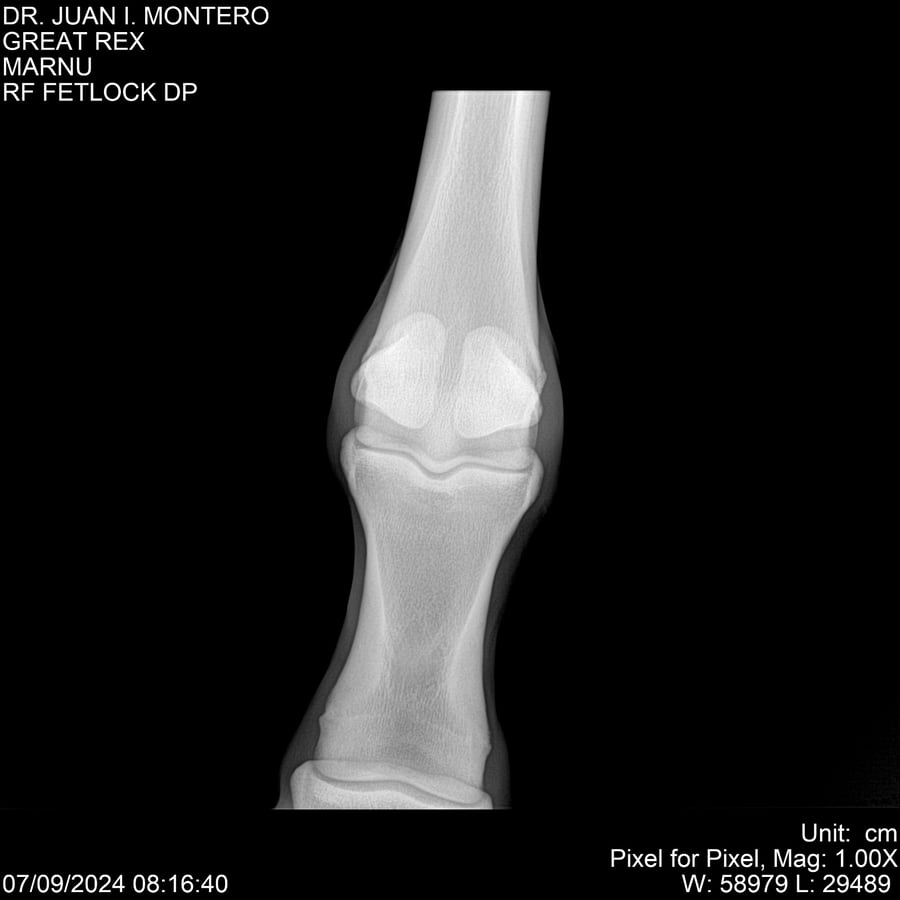

LOTE 4, GREAT REX Lote Anterior Volver al remate Lote Siguiente Ficha Contacto Montevideo - Ficha del Lote Identificador: #282518 Categoría: Yeguarizos Montevideo - 66 Visualizaciones ClicData Contacto Empresa: Abelenda N. R., Walter Hugo Nombre*: Teléfono* : E-mail* : Mensaje Enviar Registrese gratis Este contenido Exclusivo está disponible sólo para usuarios registrados Ingresar